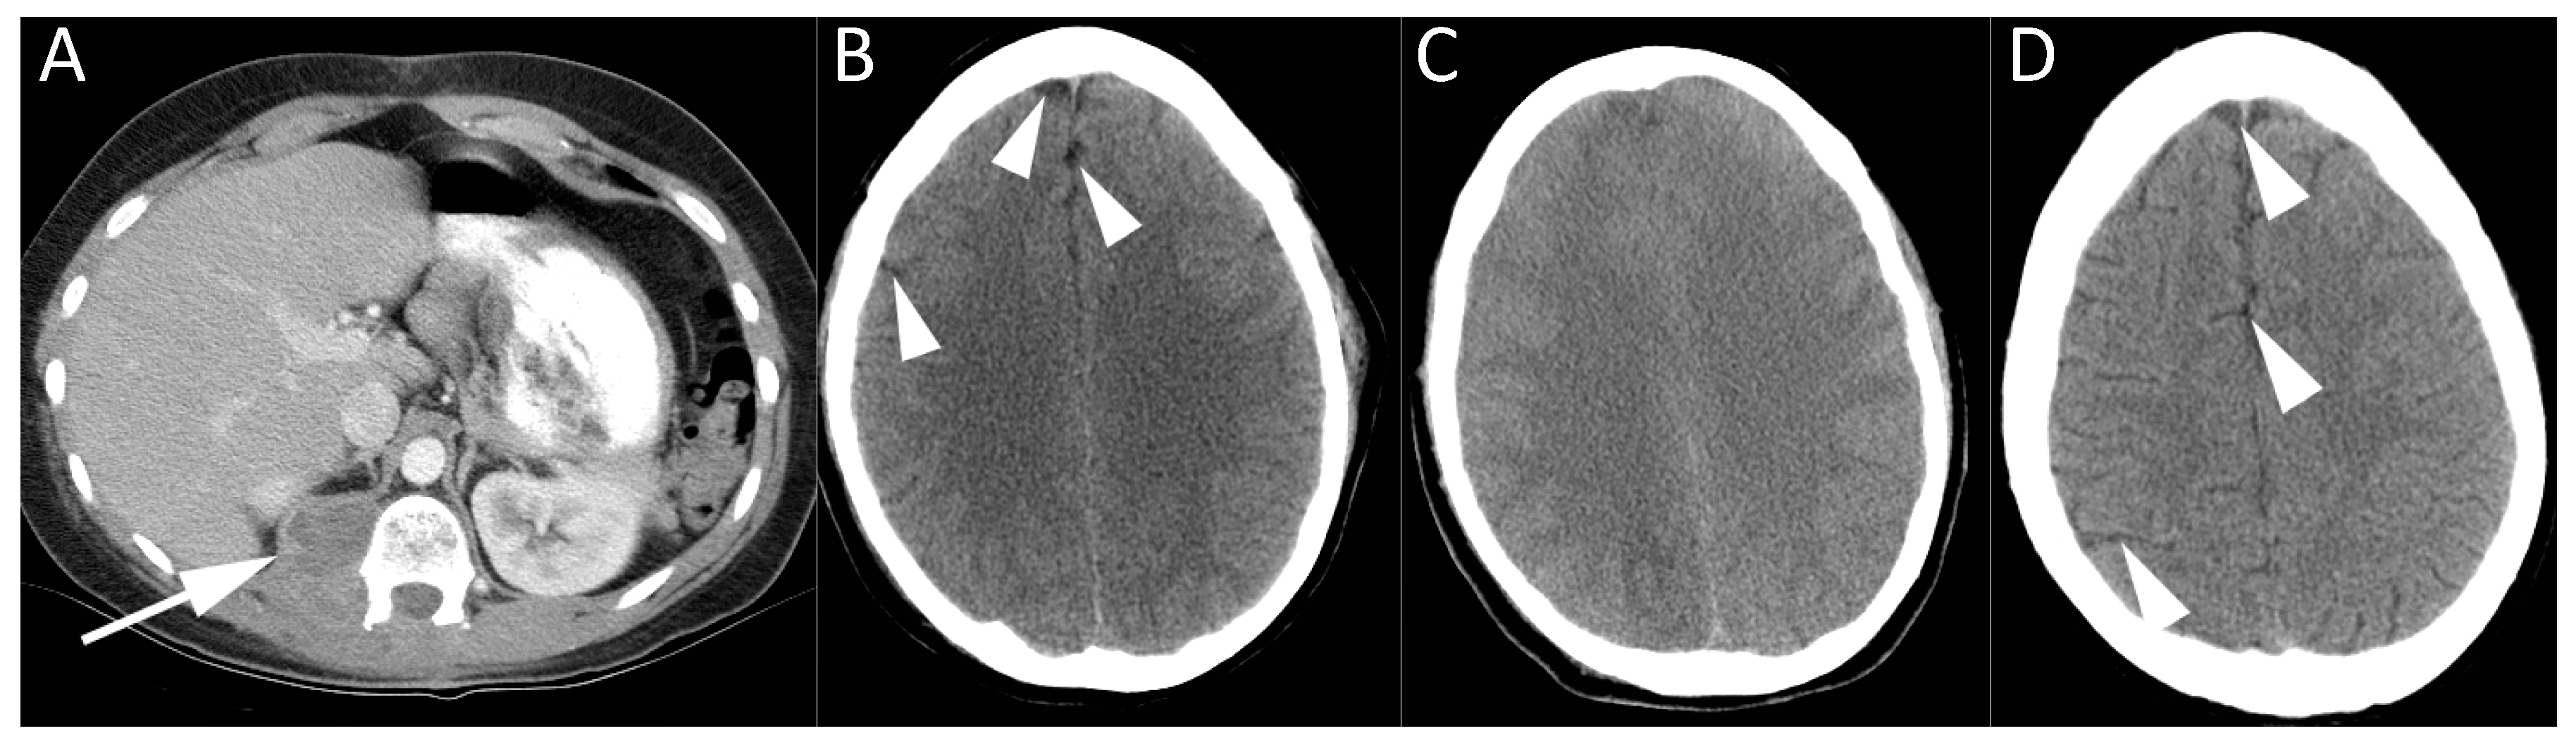

Figure 2.

CT imaging of a 20-year-old female with paraspinal tumor seen on axial contrast enhanced CT (A). She became profoundly hypotensive during spinal surgery for resection of this malignant nerve sheath tumor. Air was noted in an infusion bag. CT brain at baseline (B) was normal, revealing normal volume of cerebrospinal fluid (CSF) around the cerebral hemispheres (arrowheads). Serial CT studies of the brain performed over the coming days revealed progressively worsening cerebral edema. CT brain at three days (C) shows effacement of CSF and diffuse cerebral swelling. She was managed with hyperbaric oxygen treatment and an intracranial pressure monitor was placed. CT brain performed 19 months later showed essentially normal appearances of the brain (D), with return of normal CSF spaces (arrowheads). The patient recovered from the air embolism, but died 25 months later from metastatic disease.